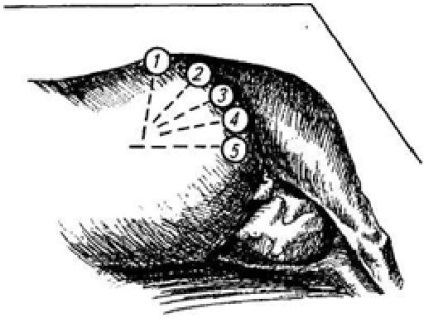

Anestezie locală: paralyum punct anestezierea I. I. magde, la care a blocat ultima intercostal (n intercostalis.), Iliohipogastric Și ilioinghinal (n ilioinguinalis.) Nervi, sau o anestezie prin infiltratie (n iliohypogastricus.). Aplicați abordările chirurgicale superioare, de mijloc și de jos din stânga. Vacile cele mai des utilizate oblic medie și secțiuni verticale, cât și din accesele inferioare - ventral-lateral. secțiune verticală începe de la partea de jos fovea de colț foame și trece parakostalno. incizie Oblique, padding pe palma makloka în direcția comună carpian. incizie ventro-laterală - de la genunchi ori peste baza ugerului, în direcția arcului de margine craniană (la o distanță de 10-12 cm deasupra venei abdominal subcutanat). Lungimea tuturor tăieturile de la vaci de 25-40 cm (Fig. 114).

Fig. 114. Cele mai frecvent utilizate abordari chirurgicale pentru cezariana secțiune transversală a vaca:

/ - medie verticală; 2- 4- oblica mediu; 5 - ventrolateral